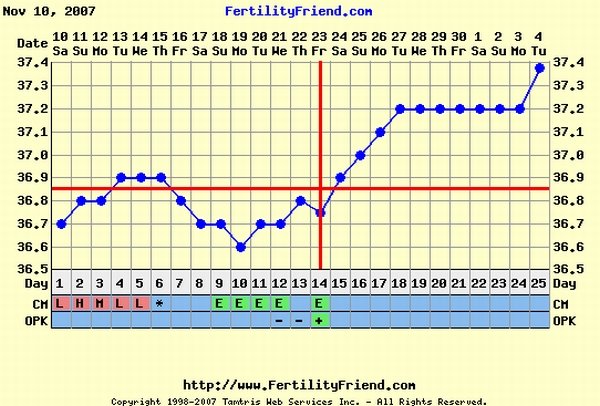

Teljesen igazad van ,hogy az első kettő is simán sikerült csak szeretgetve egymást,de azért én azt mondom adj meg minden esélyt a biztos sikerhez!!Csak mert sokaknak siekrült az első 2 simán és a 3.mégse olyan simán...ezzel nem a kedved akarom elrontani,ne érts félre,csak itt a babaneten annyi ilyet olvastam,sztem igenis meg kell tenni ezeket a praktikákat ha lehet